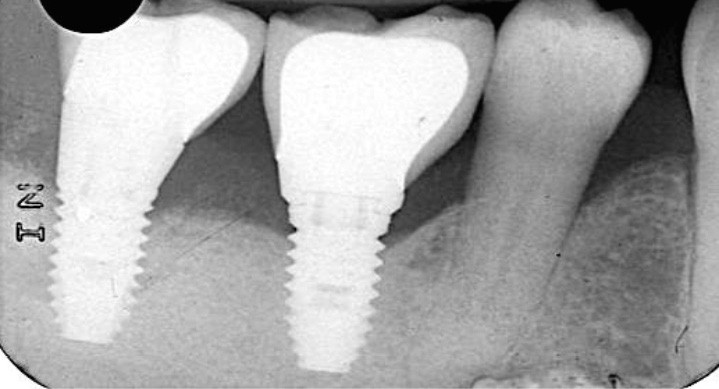

La santé des tissus péri-implantaires

Elle se définit par défaut, se traduit cliniquement par « l’absence d’inflammation, de saignement au sondage, d’œdème et de suppuration », sans tenir compte des profondeurs de sondage [4-6] (fig. 1).